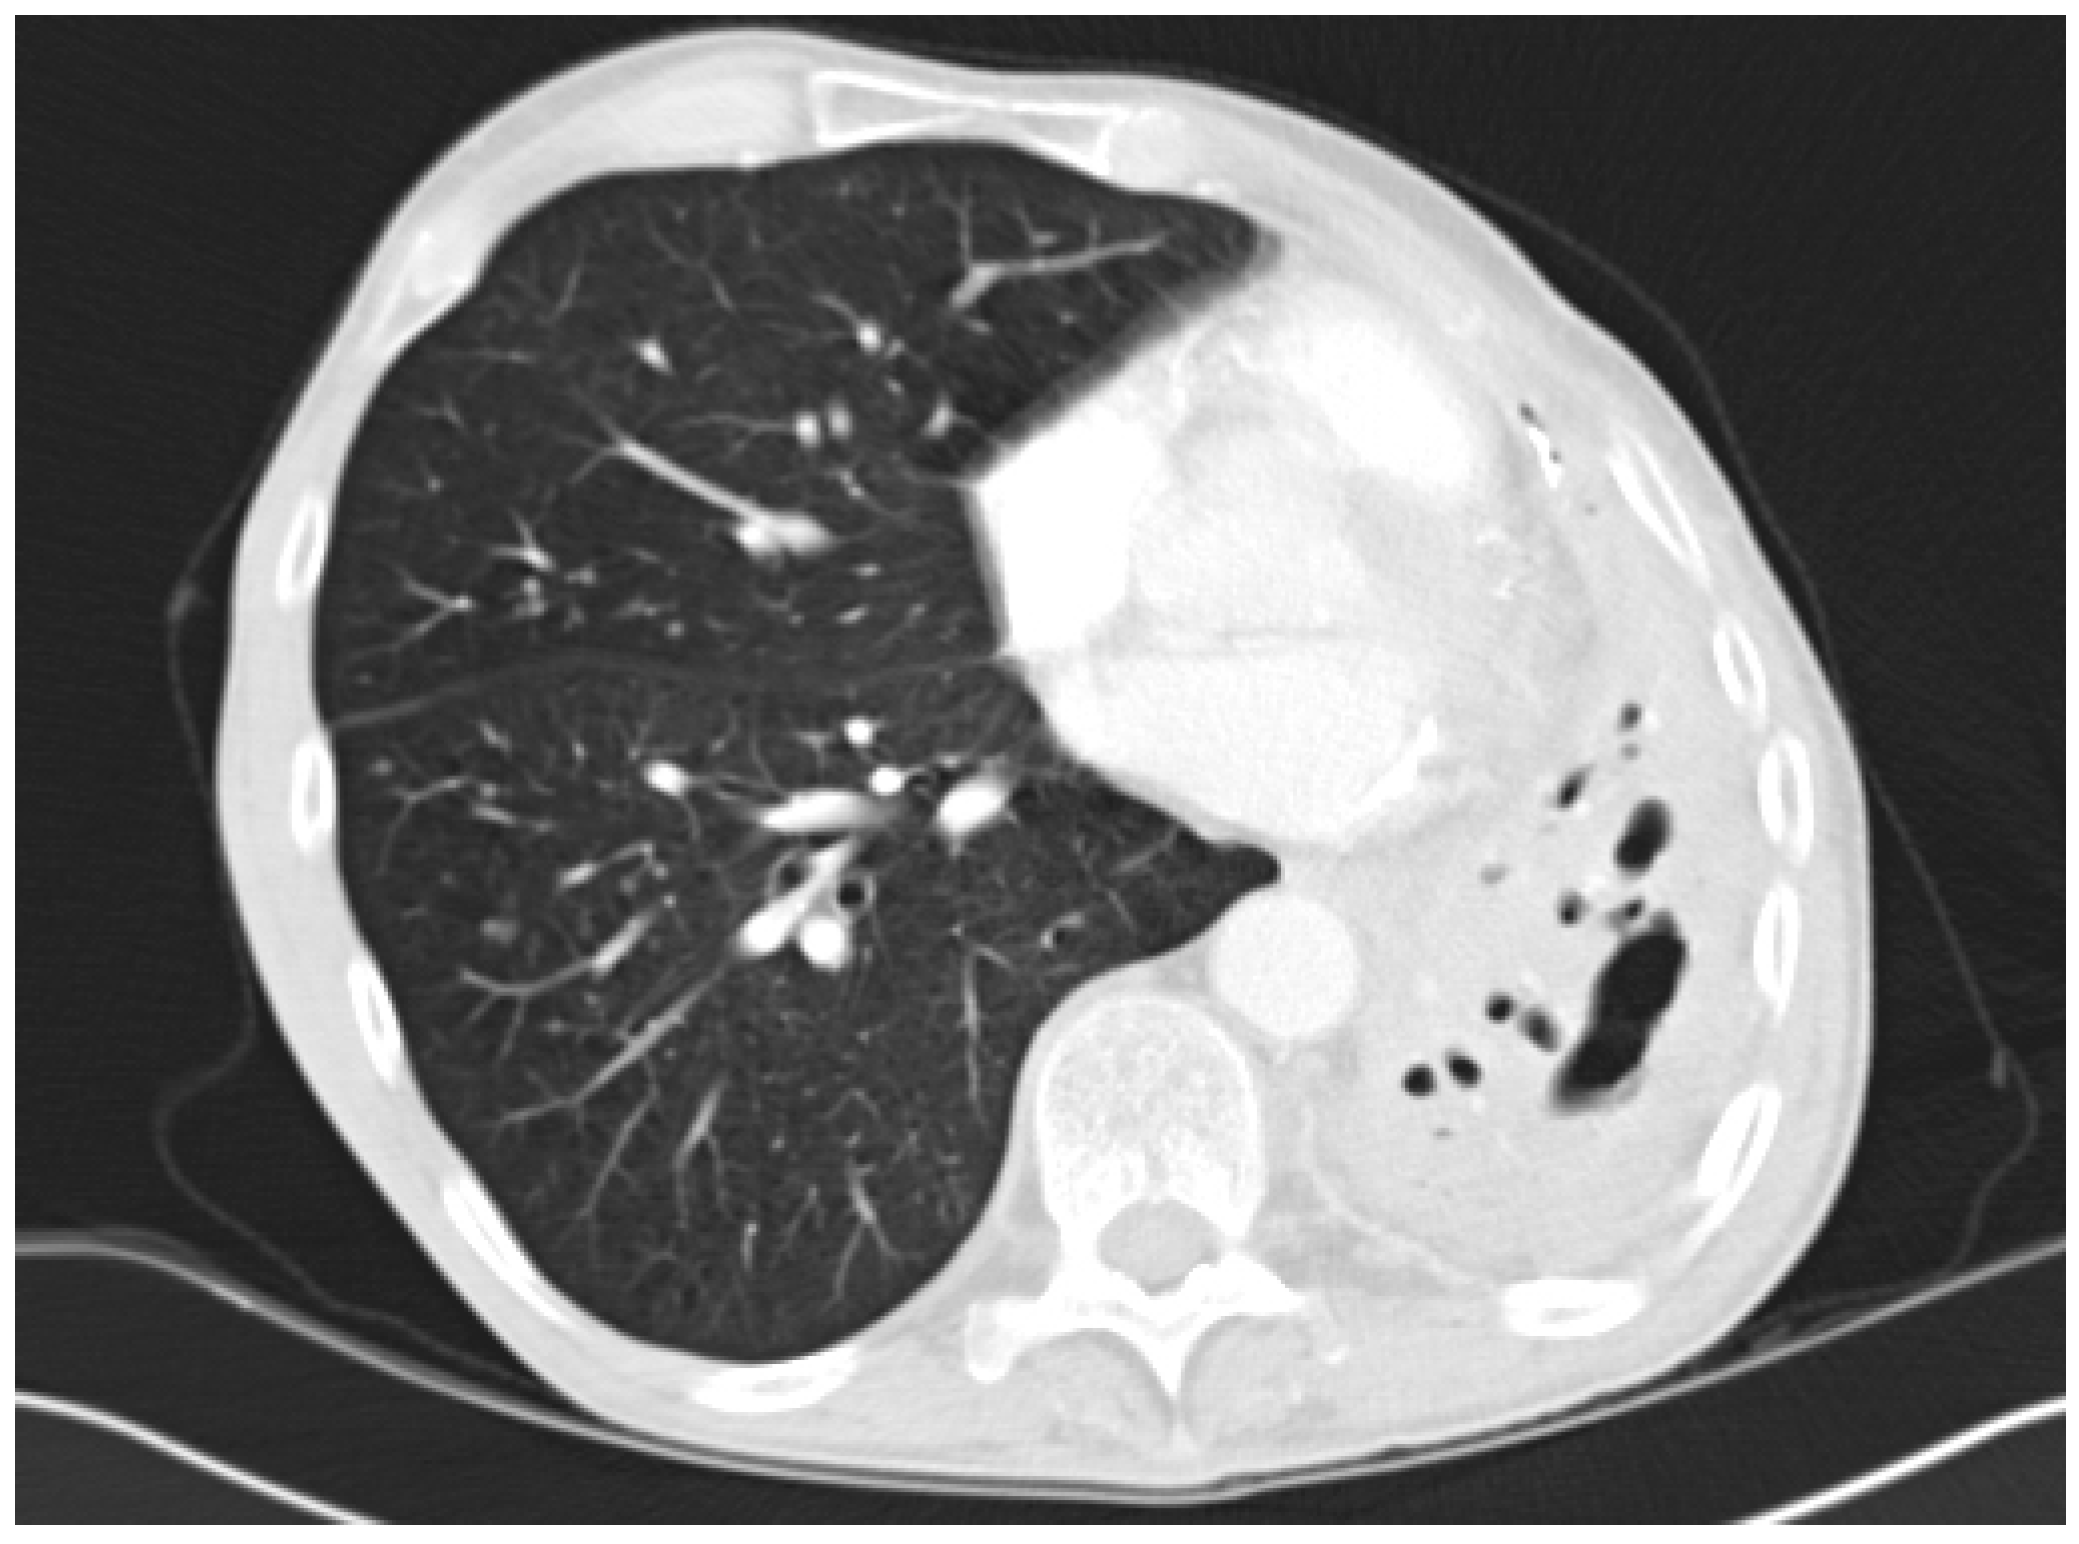

4.2. Radiology

- Desai, S.R.; Hedayati, V.; Patel, K.; Hansell, D.M. Chronic aspergillosis of the lungs: Unravelling the terminology and radiology. Eur. Radiol. 2015, 25, 3100–3107. [Google Scholar] [CrossRef] [PubMed]

- Franquet, T.; Muller, N.L.; Gimenez, A.; Guembe, P.; de La Torre, J.; Bague, S. Spectrum of pulmonary aspergillosis: Histologic, clinical, and radiologic findings. Radiographics 2001, 21, 825–837. [Google Scholar] [CrossRef] [PubMed]

- Greene, R. The radiological spectrum of pulmonary aspergillosis. Med. Mycol. 2005, 43, S147–S154. [Google Scholar] [CrossRef] [PubMed]